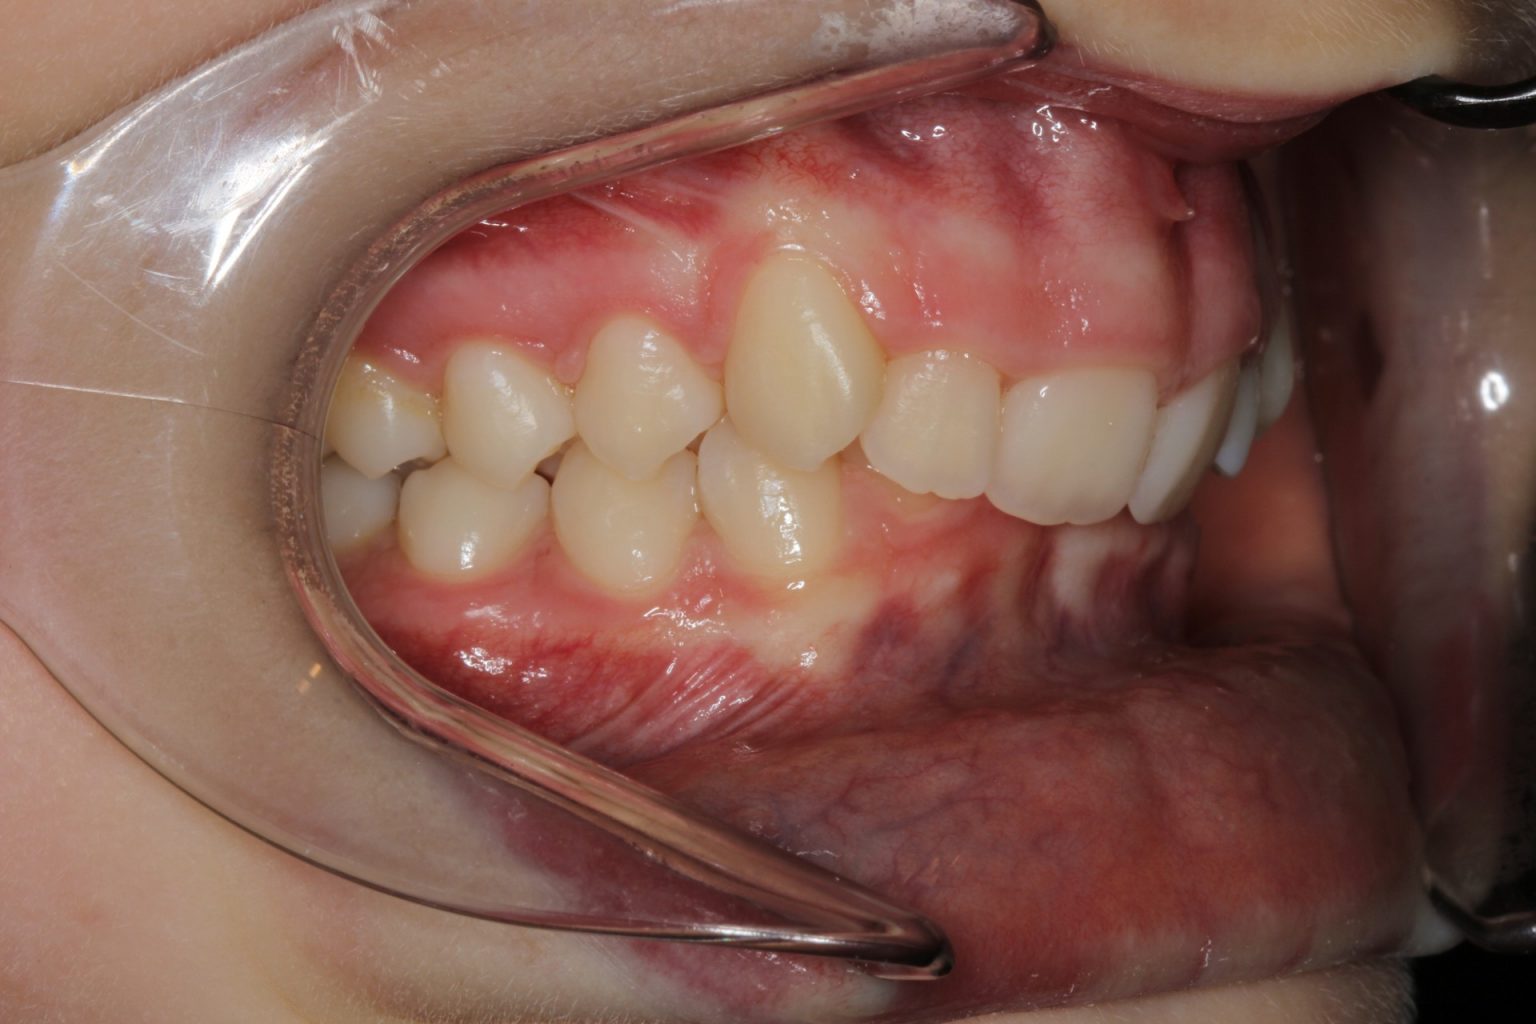

Dental Bite Problems . Your teeth may not perform vital. Get actionable strategies to adjust your bite today. Discover expert tips to recognize an off bite, understand causes, and find pain relief. Malocclusion or “bad bites” is one of the most common dental problems. There may be an underlying issue with the upper or lower jaw. It may also be referred to as: Malocclusion of the teeth is when your teeth are misaligned. Read about treatments including veneers, braces and open bite surgery on the nhs for kids and adults Bite problems, also known as malocclusions, refer to teeth misalignments or improper positioning of the jaws when biting. Malocclusion is the medical term for a bad bite, where someone’s teeth are misaligned and don’t make proper contact. With an ideal bite, the top and bottom teeth fit well together when your mouth is closed. Worried about dental open bite problems? When you have malocclusion, your upper and lower teeth don’t align when you close your mouth. This can lead to oral health complications if left untreated.